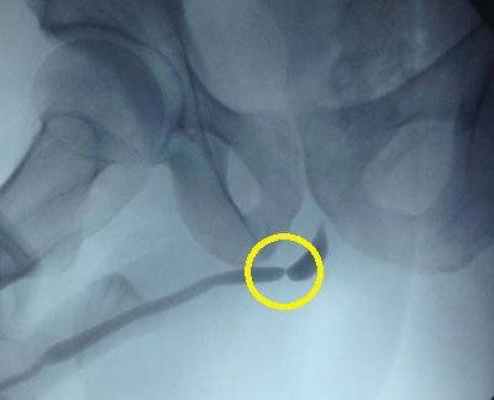

Стриктура уретры на рентгене

Для окончательного установления диагноза нужно пройти уродинамическое исследование, уретрографию восходящую и нисходящую, уретроскопию, сделать УЗИ почек и мочевого пузыря, оценить объём остаточной мочи, сдать анализы.

Недостаточно просто выявить наличие стриктуры. Необходимо уточнить, насколько сильно сужена уретра, измерить длину суженного участка и определить, в каком месте уретры он находится.

Все диагностические исследования должны быть выполнены качественно. Тогда полученные результаты становятся базой для принятия адекватных решений касательно способа и техники будущей хирургической операции.

Уретрография (восходящая и нисходящая)